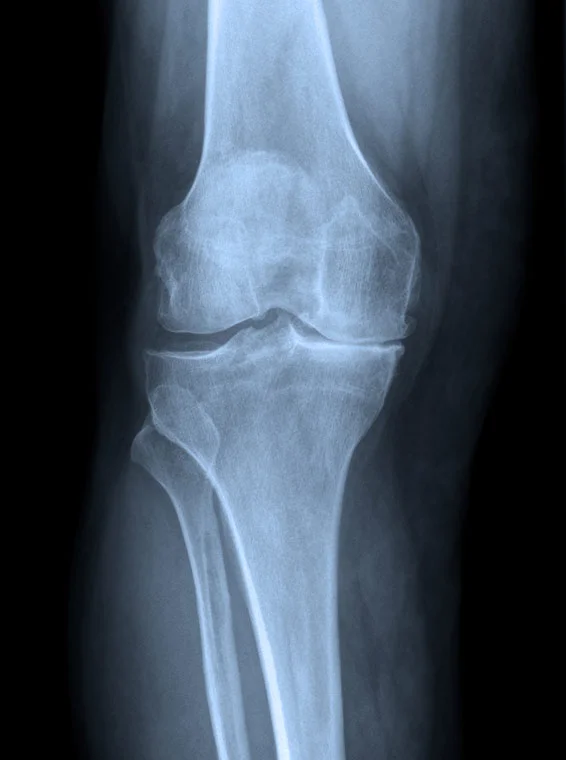

SURGICAL PROCEDURES & CONDITIONS OF THE KNEE

KNEE REPLACEMENT SURGERY

Knee replacement surgery, which is essentially resurfacing of the articular surfaces of the joint and reducing inflammation and therefore pain in the knee, has a high success rate in relieving symptoms. Approximately ninety-five out of every hundred joint replacement procedures give good pain relief for a prolonged period of time following the surgery. Knee replacement procedures have become more common due to the aging population.

FULL KNEE REPLACEMENT

• In those patients where there is arthritis throughout the knee which is severe, a full knee replacement will be recommended.

PARTIAL OR UNICOMPARTMENTAL KNEE REPLACEMENT

• In those patients with only limited arthritis in one part of the knee, the partial knee replacement procedure may be possible. The advantages of a partial knee replacement are that the procedure is a smaller operation with faster recovery time.